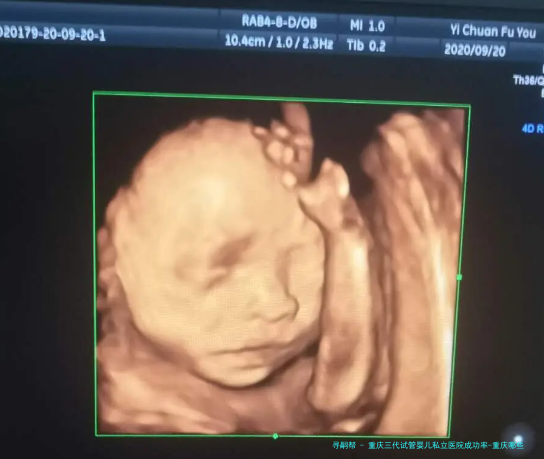

通过对此医院过去五个年头实施的三代试管项目进行统计数据解析,我们可以看到其成功率远高于全国平均水平。在该医院实施的三代试管婴儿项目中,成功率达到了75%之上,大大超出国内其他私立医院。这一成绩受益于医院引进了最先进设备和技术,并严格按照国际规范进行操作。